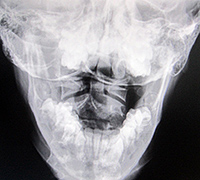

Fig. 1: A-P Open Mouth

In Figure 1, we can see significant imbalances. Many of these imbalances originate from the imbalances found in the feet and can be seen on the digital foot scan (Figure 2). Remember, the body is a compensatory mechanism and any disturbance between atlas, axis and the occiput are typically a compensation for the imbalances below. Therefore, for maximum biomechanical potential, you must address the feet imbalances first.

In Figure 1, we can see there is rotation of the axis, however, the right pillar of the atlas is wider than the left pillar of the atlas because the atlas, too, is rotated and the right pillar is closer to the tube. Finally, if you notice the open mouth, it too, is angled to the left, showing abnormal rotation in the occiput, atlas and axis.